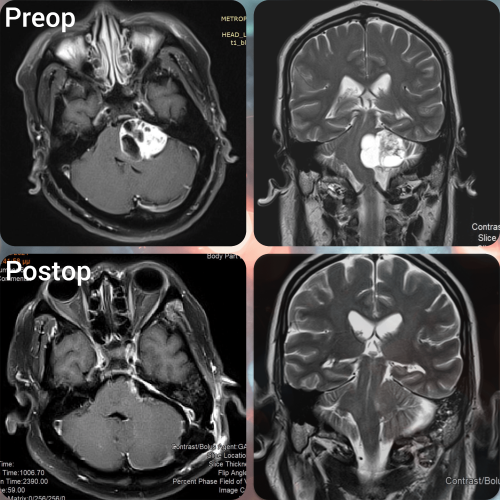

Το ακουστικό νευρίνωμα ή αλλιώς αιθουσαίο σβάννωμα είναι ένας καλοήθης όγκος του ακουστικού νεύρου, δηλαδή του νεύρου πηγαίνει από τον εγκέφαλο στις δομές του έσω ωτός. Μπορεί να προκαλέσει προβλήματα όπως απώλεια ακοής και διαταραχές ισορροπίας.Τα ακουστικά νευρινώματα είναι πιο συχνά στους ενήλικες από ότι στα παιδιά. Συνήθως εμφανίζονται μονόπλευρα, δηλαδή μόνο σε μία πλευρά, αλλά μερικοί ασθενείς μπορεί να παρουσιάσουν και στα δύο ακουστικά νεύρα.